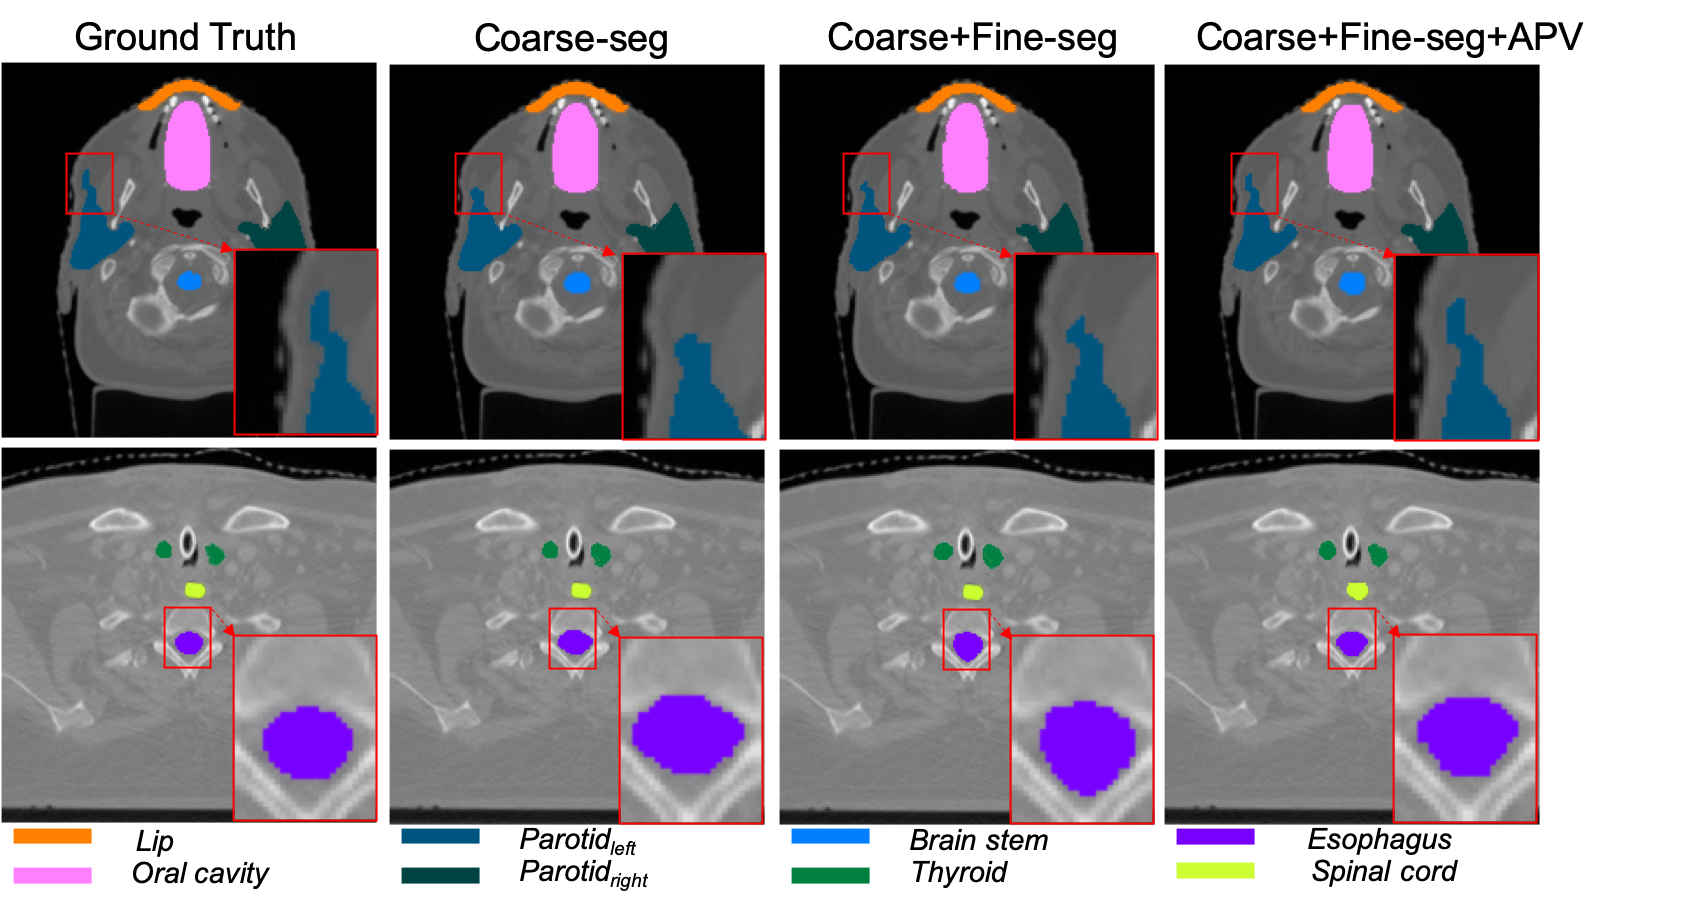

Refer to caption

Figure 6: Example results of multi-organ segmentation on the instituted head-and-neck dataset.

Tab. 3 illustrates an ablation study on the instituted H&N dataset, where the accuracy (average DSC(%)) of coarse-scale, fine-scale and APV refined segmentation are reported. Compared with [40] that processes on 2D images in fine-scaled segmentation, our method has made a improvement (12%1percent21~{}2\% DSC) in the fine-scaled segmentation since it performs directly on 3D volume for all reported OARs, including some challenging organs (e.g. brain stem, esophagus, spinal cord and etc.) that are explored by little research. The relatively low accuracy in some OARs test is mainly caused by lack of organ annotations. For instance, only 6 over 56 body samples contain larynx annotation in ground truth so that all tests on this category shows a low accuracy. Moreover, it can be observed that our proposed method leads to a significant improvement (15%1percent51~{}5\%) in segmentation precision for all considered organs by leveraging adversarial cues provided by the APV. Though all experimental results of different organs increase after applying the APV, the validator assists the segmentation network get a larger improvement (Our-A) when the base model (Our-F) has difficulty (i.e. 4%percent44\% increment in accuracy of Larynx segmentation). Meanwhile, as illustrated in Fig. 6, the qualitative measurement visually compares the segmentation results of the 8 H&N OARs between the proposed base model without and with APV module. The refined segmentation by APV (Our-A) provides more integrated and consistent results, because the segmentation network is forced to segment details of OARs to ensure that no organ information is detected by APV module. The visual observation reflects that the validation network contributes to accurate segmentation in details.